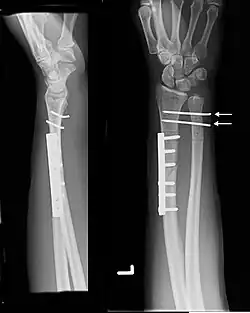

Galeazzi fracture

| Galeazzi fracture-dislocation | |

| Galeazzi fracture. Arrow points at the dislocated ulnar head | |

The Galeazzi fracture is a fracture of the distal third of the radius with dislocation of the distal radioulnar joint. It classically involves an isolated fracture of the junction of the distal third and middle third of the radius with associated subluxation or dislocation of the distal radio-ulnar joint; the injury disrupts the forearm axis joint.[1]